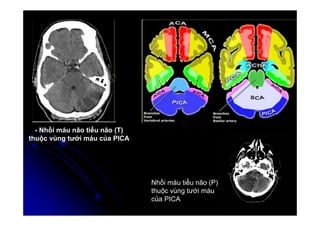

- Nhồi máu não tiểu não (T)

thuộc vùng tưới máu của PICA

Nhồi máu tiểu não (P)

thuộc vùng tưới máu

của PICA